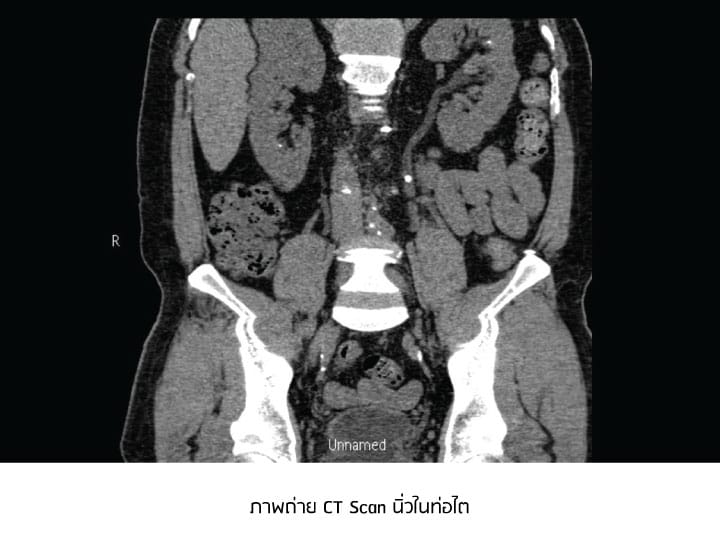

การวินิจฉัย ทำได้โดยการตรวจเลือด ตรวจปัสสาวะ และการตรวจทางรังสีวินิจฉัยด้วยเครื่องเอกซเรย์คอมพิวเตอร์ช่องท้อง หรือที่เรียกว่าการทำซีทีสแกน (CT Scan)